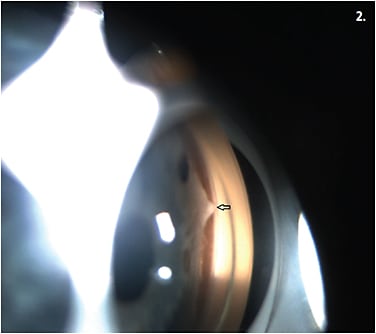

• Axenfeld-Rieger. This syndrome is characterized by abnormal iris appearance, an anteriorly displaced Schwalbe’s line (posterior embryotoxon) and iris strands to Schwalbe’s line (Figures 1 and 2). These patients can have craniofacial and dental abnormalities. Occasionally, these patients have pituitary abnormalities and cardiac anomalies.

Figure 2. A gonioscopic photo depicting iris adhesion to Schwalbe’s line (arrow) in a patient with Axenfeld-Rieger Syndrome.